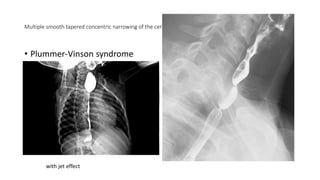

Multiple smooth tapered concentric narrowing of the cervical esophagus in keeping with esophageal webs.

• Plummer-Vinson syndrome

with jet effect